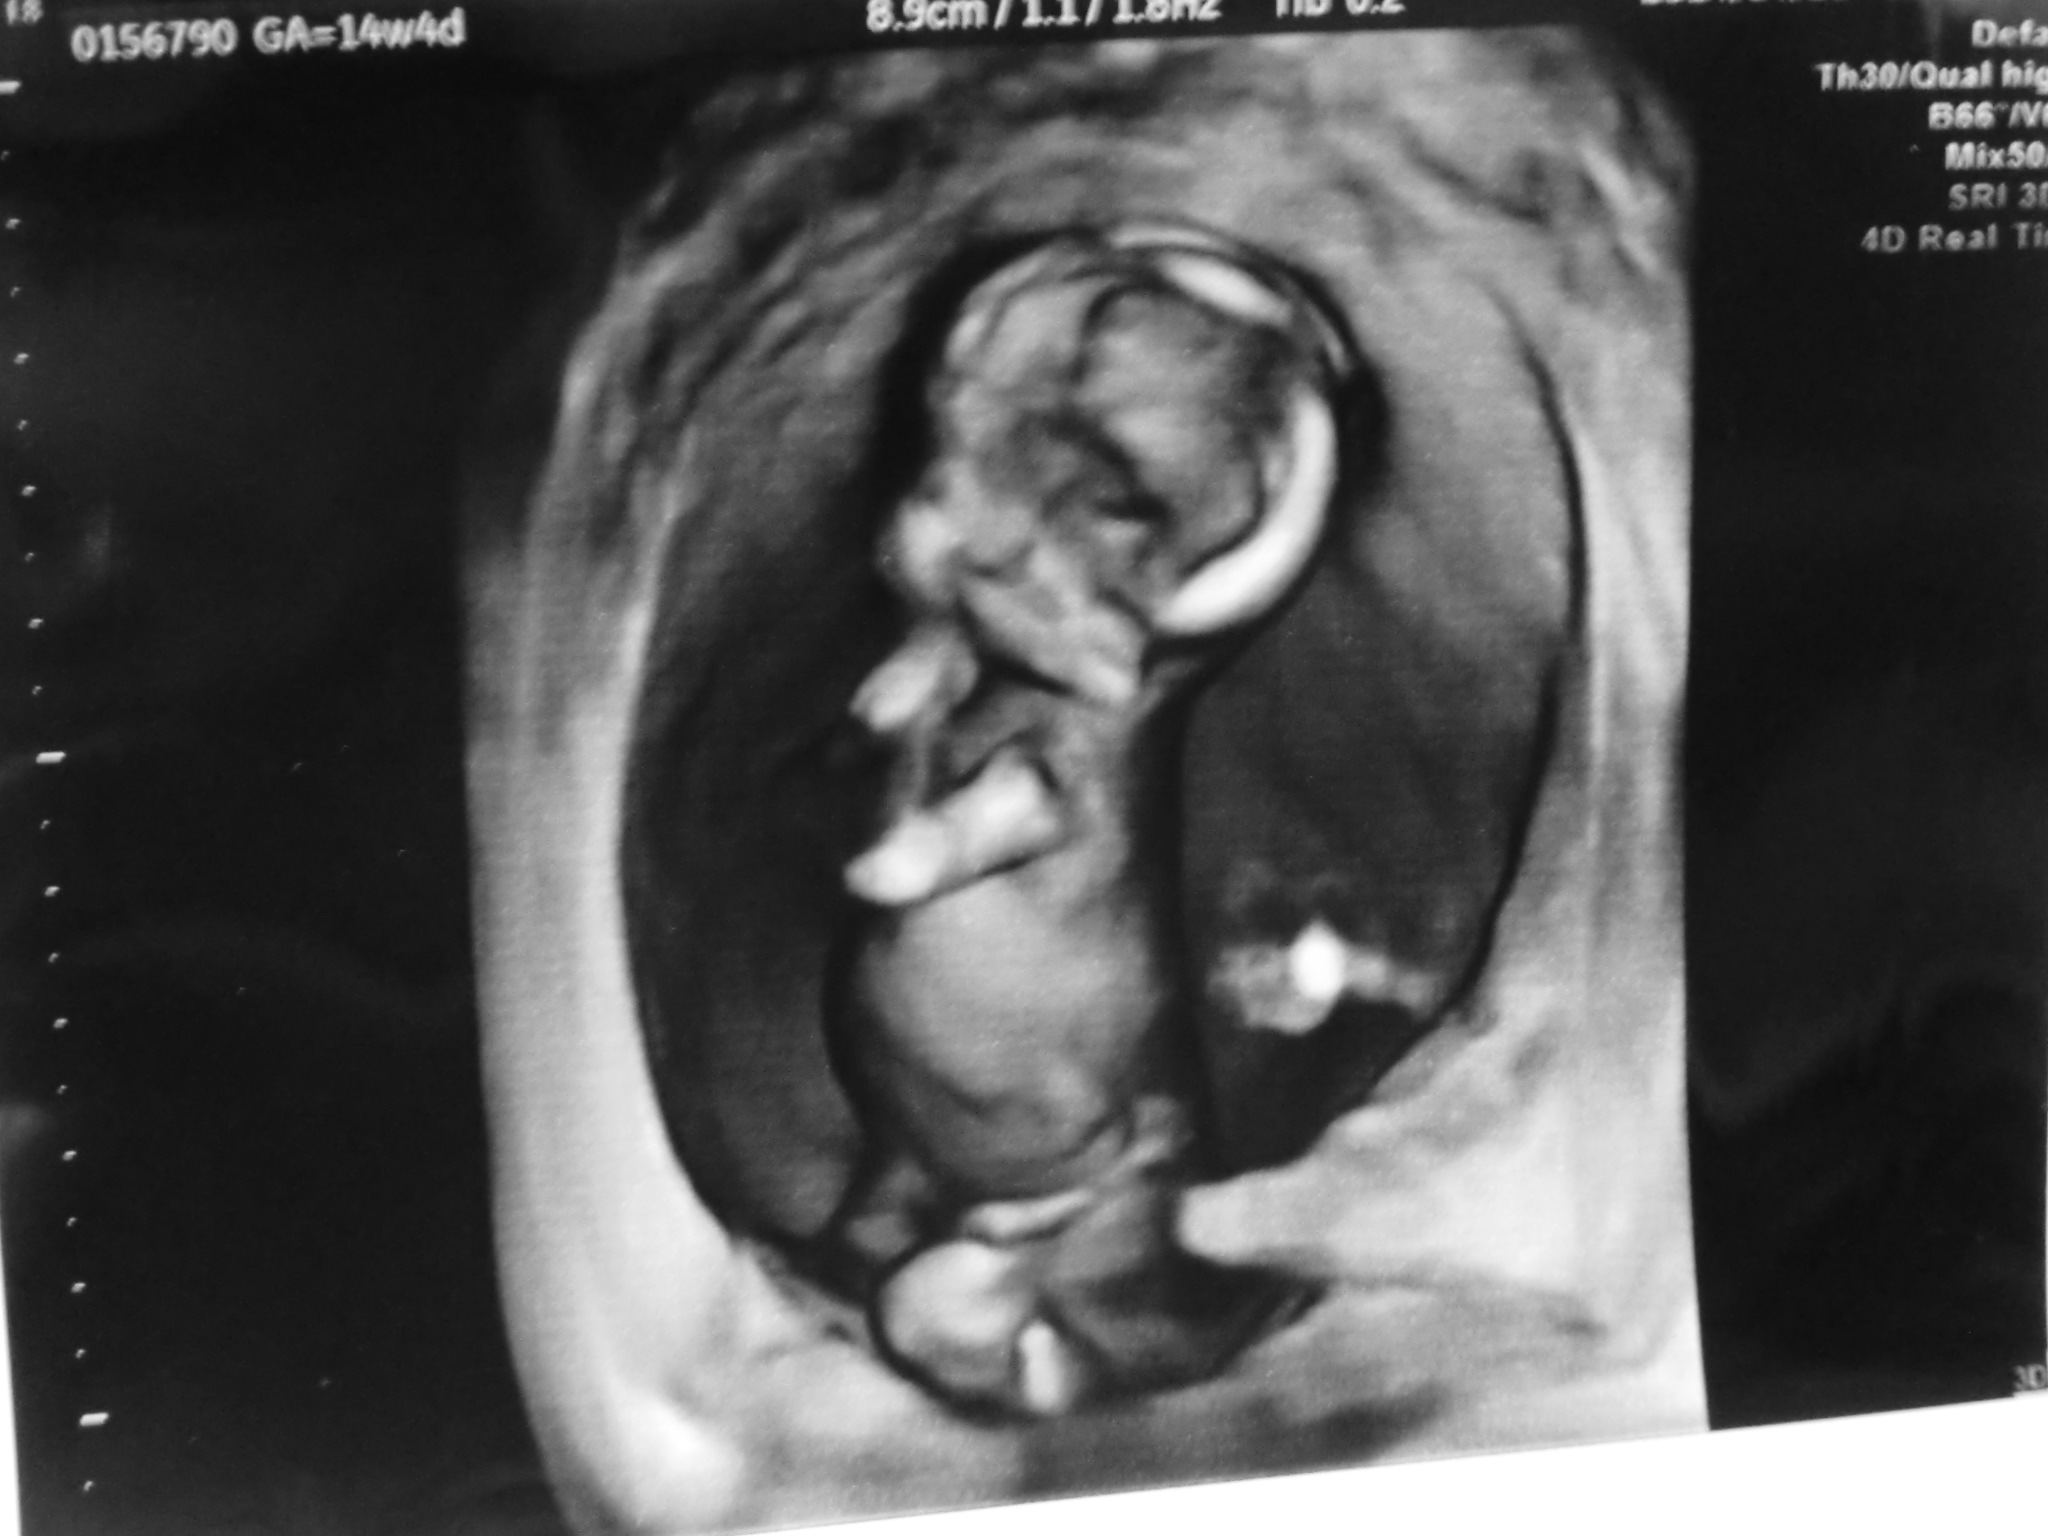

今日は病院で、エコーの映像をDVDに録画してくれる日だったんだけど、今までの男の先生じゃなくて、知らない女の先生で、いつもの人が良かったです。私が慣れてるから。

DVDも、4Dのほのぼのと素人が見ても楽しめるものになるかと勝手に期待してたけど、

なんらいつもと変わらないただの検診映像をそのまま録画してるだけで、無音だし、4Dでもないし、

なんならいつもより輪切り映像ばっかで身体のどの部位だかが説明受けてないとわからないし、

ちらっと4Dに切り替えてくれたけど、顔のアップだけで全体を映してくれない。。

で、顔アップで、胎児がこっち向いてくれそうにないから、すぐまた元の白黒画像に戻された。

どれだけやるのか分からないから、この後映してくれるのかどうか分からないから、もっと撮って!とか言えんし(そもそもそんな事言って良いのかわからんし)

なんだかよくわからんかんじのDVDになりました。

録画が次に出来るのは30週頃の検診でだそうなので、今後毎回出来るわけではないようです。

この病院は千円かかるしね。

でも妊婦は市から定期検診代の補助が出るので、検査によりますが、今回の支払いは1080円だけでした(つまりDVD代だけ)